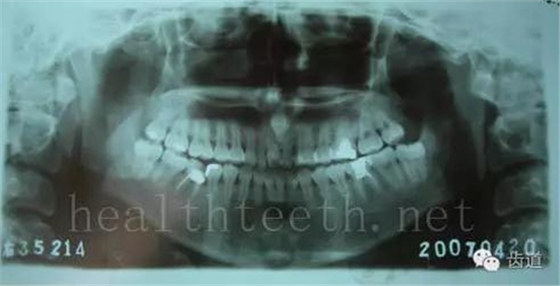

40歲人的口腔狀況